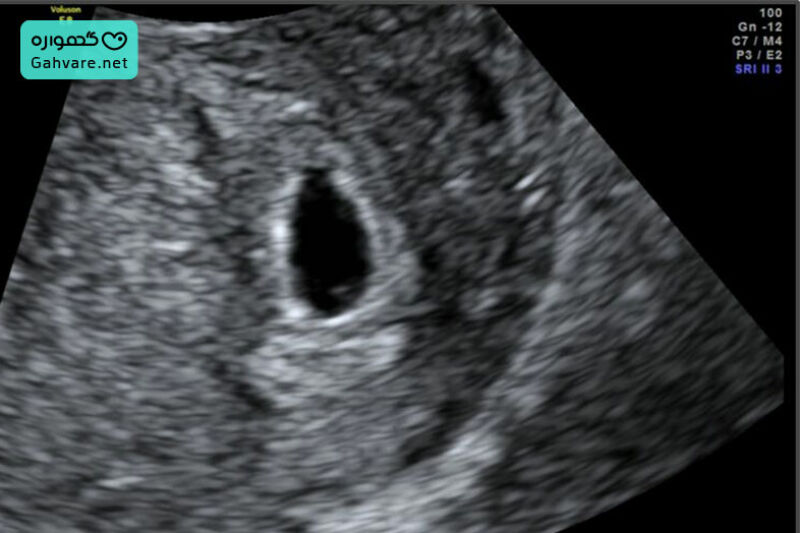

- سونوگرافی واژینال: انجام سونوگرافی واژینال در این هفته رایجتر است، زیرا سونوگرافی شکمی هنوز بهخوبی قادر به نشان دادن ساختارهای اولیه نیست. در سونوگرافی هفته پنجم معمولاً کیسه حاملگی (Gestational Sac) و گاهی کیسه زرده قابل مشاهده است، اما معمولاً هنوز ضربان قلب جنین مشخص نمیشود و برای شنیدن آن باید تا هفته ۶ یا ۷ صبر کرد. این سونوگرافی کمک میکند بارداری داخل رحم تأیید شود و احتمال حاملگی خارجرحمی بررسی گردد.

- کیسه حاملگی: مشاهده کیسه حاملگی و رشد اولیه آن در سونوگرافی برای تأیید بارداری سالم.